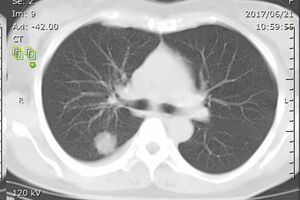

「これはおかしいとすぐにCTを撮って。検査後、診察室で写し出された画像には、2センチほどの腫瘍が2つ写っていました。当時私は、担当の呼吸器内科の先生と仕事でも親しく、レントゲン写真やCTの見方を教えてもらっていたんです。なので画像を見て肺がんだとすぐにピンときました。ショックでしたね」